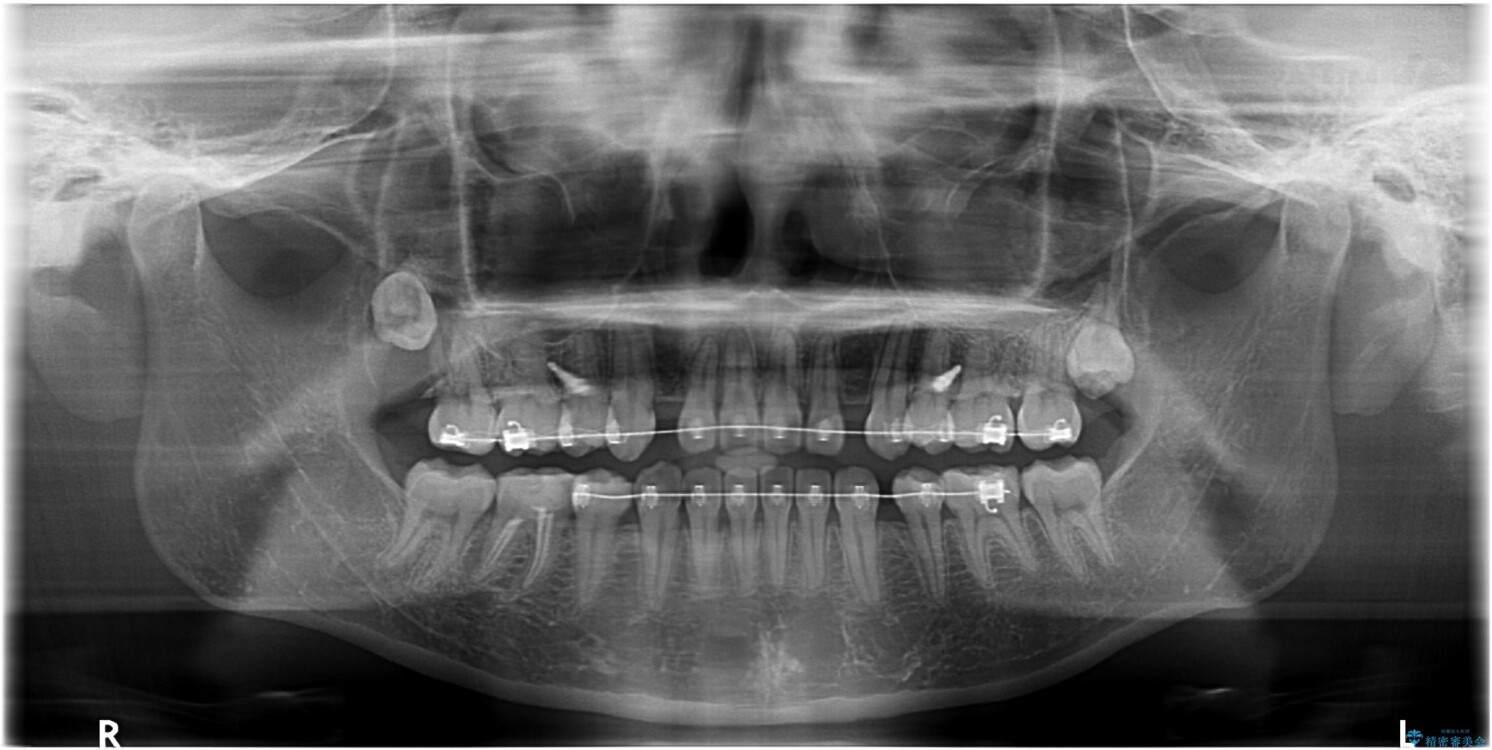

治療前

• 転勤でも安心して治療継続 抜歯スペース閉鎖と深い噛み合わせ改善のワイヤー矯正 治療前画像